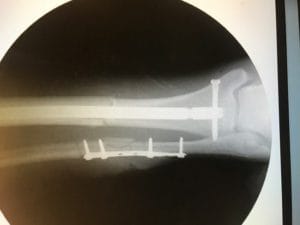

I asked a few questions and understood they would drill out the bone marrow from my tibia then drive a titanium rod into the center to provide stability. Given the multiple breaks; pins and plates would be attached to help with healing. I would be in a cast then boot from 4 to 8 weeks. Rehab would be key to my recovery. I should be as good as I am today in about a year.